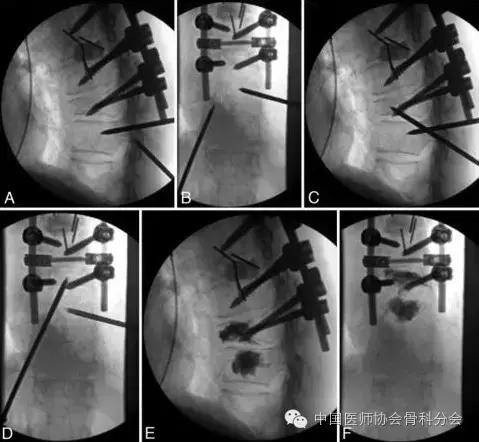

图3. 病例1.术中的正位X线片。A和B:胸10椎体穿刺完成。穿刺点在椎弓根的下后外侧。C和D:穿刺针进入胸9椎体中部。E和F:骨水泥注入以后有少量进入胸9/10椎间隙